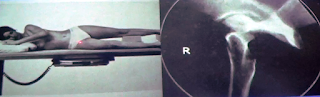

En la imagen de abajo apreciamos el posicionamiento del paciente que ingresa a la sala

radiológica en camilla con una presunta fractura de fémur. En este tipo de

proyección solamente obtendremos una imagen parcial del fémur (tercio distal y

tercio medio).